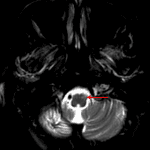

Age: 67

Sex: Female

Indication: Ataxia

Chronic lymphocytic inflammation with pontine perivascular enhancement responsive to steroids (CLIPPERS)